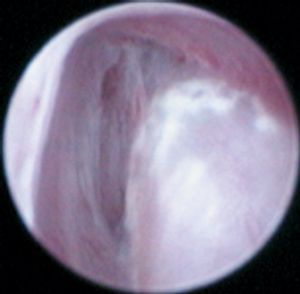

A 7-month-old intact male Labrador retriever was presented for evaluation of a two-week history of left hindlimb lameness.